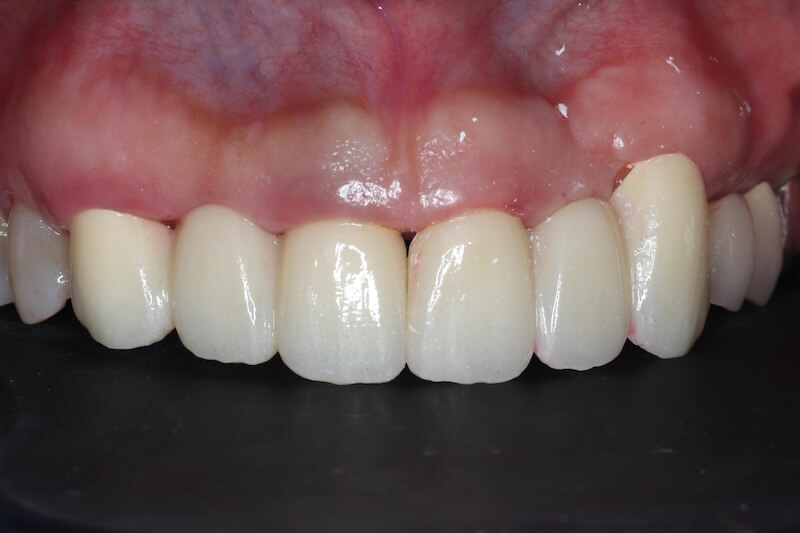

治療成果分享:重獲健康的牙齦與自然美齒

手術完成後的兩三個月左右,製作正式的假牙。最終的假牙我們設計成兩組正中門牙和犬齒相連的牙橋,和原來六顆連在ㄧ起的設計相比,清潔會相對容易很多。Ms.H 對治療前後的明顯感受是:牙齦牙周的問題獲得滿意的解決以外,新的假牙的美觀度也有大幅的改善,花時間好好投資在自己身上,非常值得。未來規律定期回診好好的維護,相信能夠常保健康穩定的治療成果。